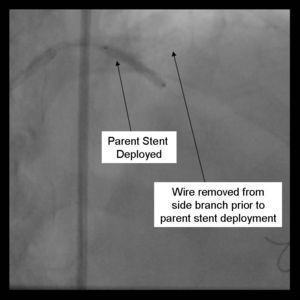

9) The parent stent is deployed.

10) The side-branch is rewired. It is sometimes necessary to change wires to either a hydrophilic wire eg. Whisper, (Guidant, Temecula, California) or Pilot 50 or 150 (Guidant, Temecula, California), or ASAHI Fielder (Abbott Vascular Devices, Redwood City, California), one of increasing stiffness eg. ASAHI Miracle Bros 3 (Abbott Vascular Devices, Redwood City, California), or both eg. Shinobi (Guidant, Temecula, California) or Confienza(Abbott Vascular Devices, Redwood City, California).